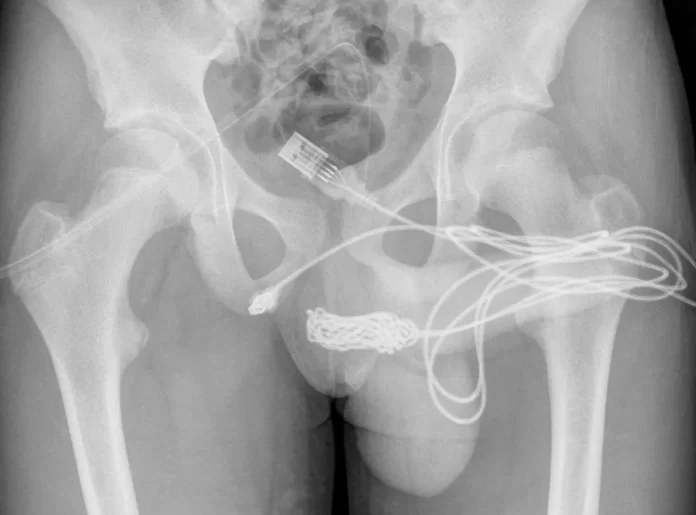

El curioso experimento no tuvo éxito: una vez que comenzó a orinar sangre, sus padres lo llevaron al hospital.Al examinar al joven, de 15 años, los médicos del University College Hospital de Londres vieron que el cable había quedado en su escroto, como si fuera un catéter electrónico. La radiografía reveló que tenía un verdadero nudo dentro de sus genitales.

El propio adolescente, avergonzado, contó a los doctores que se había insertado el cable en la uretra para medir la longitud de su pene «por curiosidad sexual» y había intentado sacarlo por sí mismo.

Para extraer el nudo, los médicos tuvieron que hacer una incisión entre el pene y el ano del paciente.